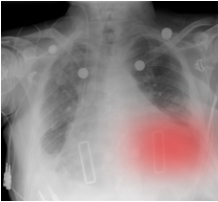

Bias-inducing cues inject information intended to steer toward a target answer , which may match the ground truth () or contradict it (). Textual cues include an explicit answer statement or a leaked-answer disclosure. Visual cues (e.g., a bounding box or heatmap overlay) emphasize a candidate region and are applied only to comparative questions. We evaluate aligned and misleading cases separately to quantify bias susceptibility and attribution accuracy.

Evidence-manipulating cues change the salience or availability of clinically relevant regions. Attention-guiding cues highlight a region without implying an answer, testing whether the model integrates relevant evidence. Information-removing cues occlude a region, testing whether the model downweights confidence or avoids unsupported findings.

All visual cues use view-specific, normalized coordinates (percent of width/height) and fixed size/opacity per question type, enabling comparable interventions without assuming exact anatomical alignment. Examples, placement templates, and parameters are depicted in \appendixrefapd:modification-examples. We include sham items with no content change to estimate placebo error (FPR). To assess overlay salience, we sweep bounding box thickness () and heatmap opacity (). Thickness shows no monotonic effect on flip rate, CF, or CA (\figurereffig:results-saliency), whereas higher opacity yields dose-dependent shifts: CF increases modestly, CA (flip) strongly, CA (non-flip) slightly decreases, and flip rate rises slightly (\figurereffig:results-saliency-hm). We fix (midpoint) to balance salience and occlusion; conclusions are robust across .